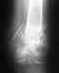

Перелом пятой плюсневой кости

Ломала пятую плюсневую со смещением и раздроблением.сделали оперцию поставили пластину см 7-8.спустя год кость срослась и я ее сняла.после второфй операции прошло 2 месяца.шов был косметический саморассасывающийся.самочувствие хорошое.нога не беспокоит.лишь иногда ноет.от усталости толи от смены погоды.вопрос: когда можно носить высокие каблуки?заниматься активно спортом?